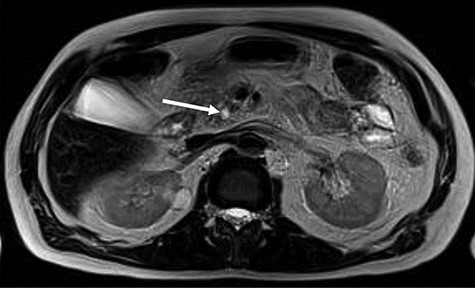

MRI, 1 week after, showed a benign well-circumscribed nodular lesion in the head of the pancreas without contrast enhancement and associated pancreatic stones (Fig. 1).

MRI—hyposignal focus within the main pancreatic duct in the cephalic region, measuring 0.6 cm, associated with irregular dilation of the upstream duct, suggesting stone (arrow).